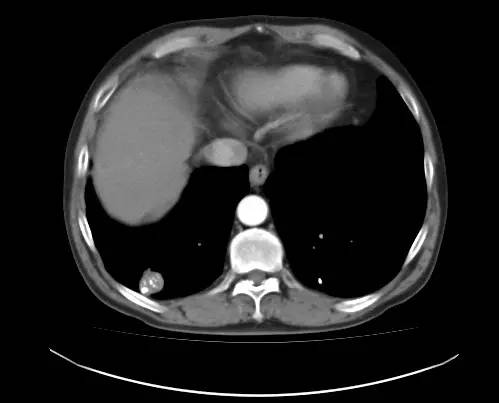

男,52岁,查体发现肺部病变

[影像描述]

右肺下叶结节样病变,内有钙化、脂肪成分,增强后可见轻度强化。

[检查结果]

右肺下叶错构瘤.

右肺下叶病变内有钙化、脂肪成分,典型爆米花样钙化,增强后可见轻度强化。